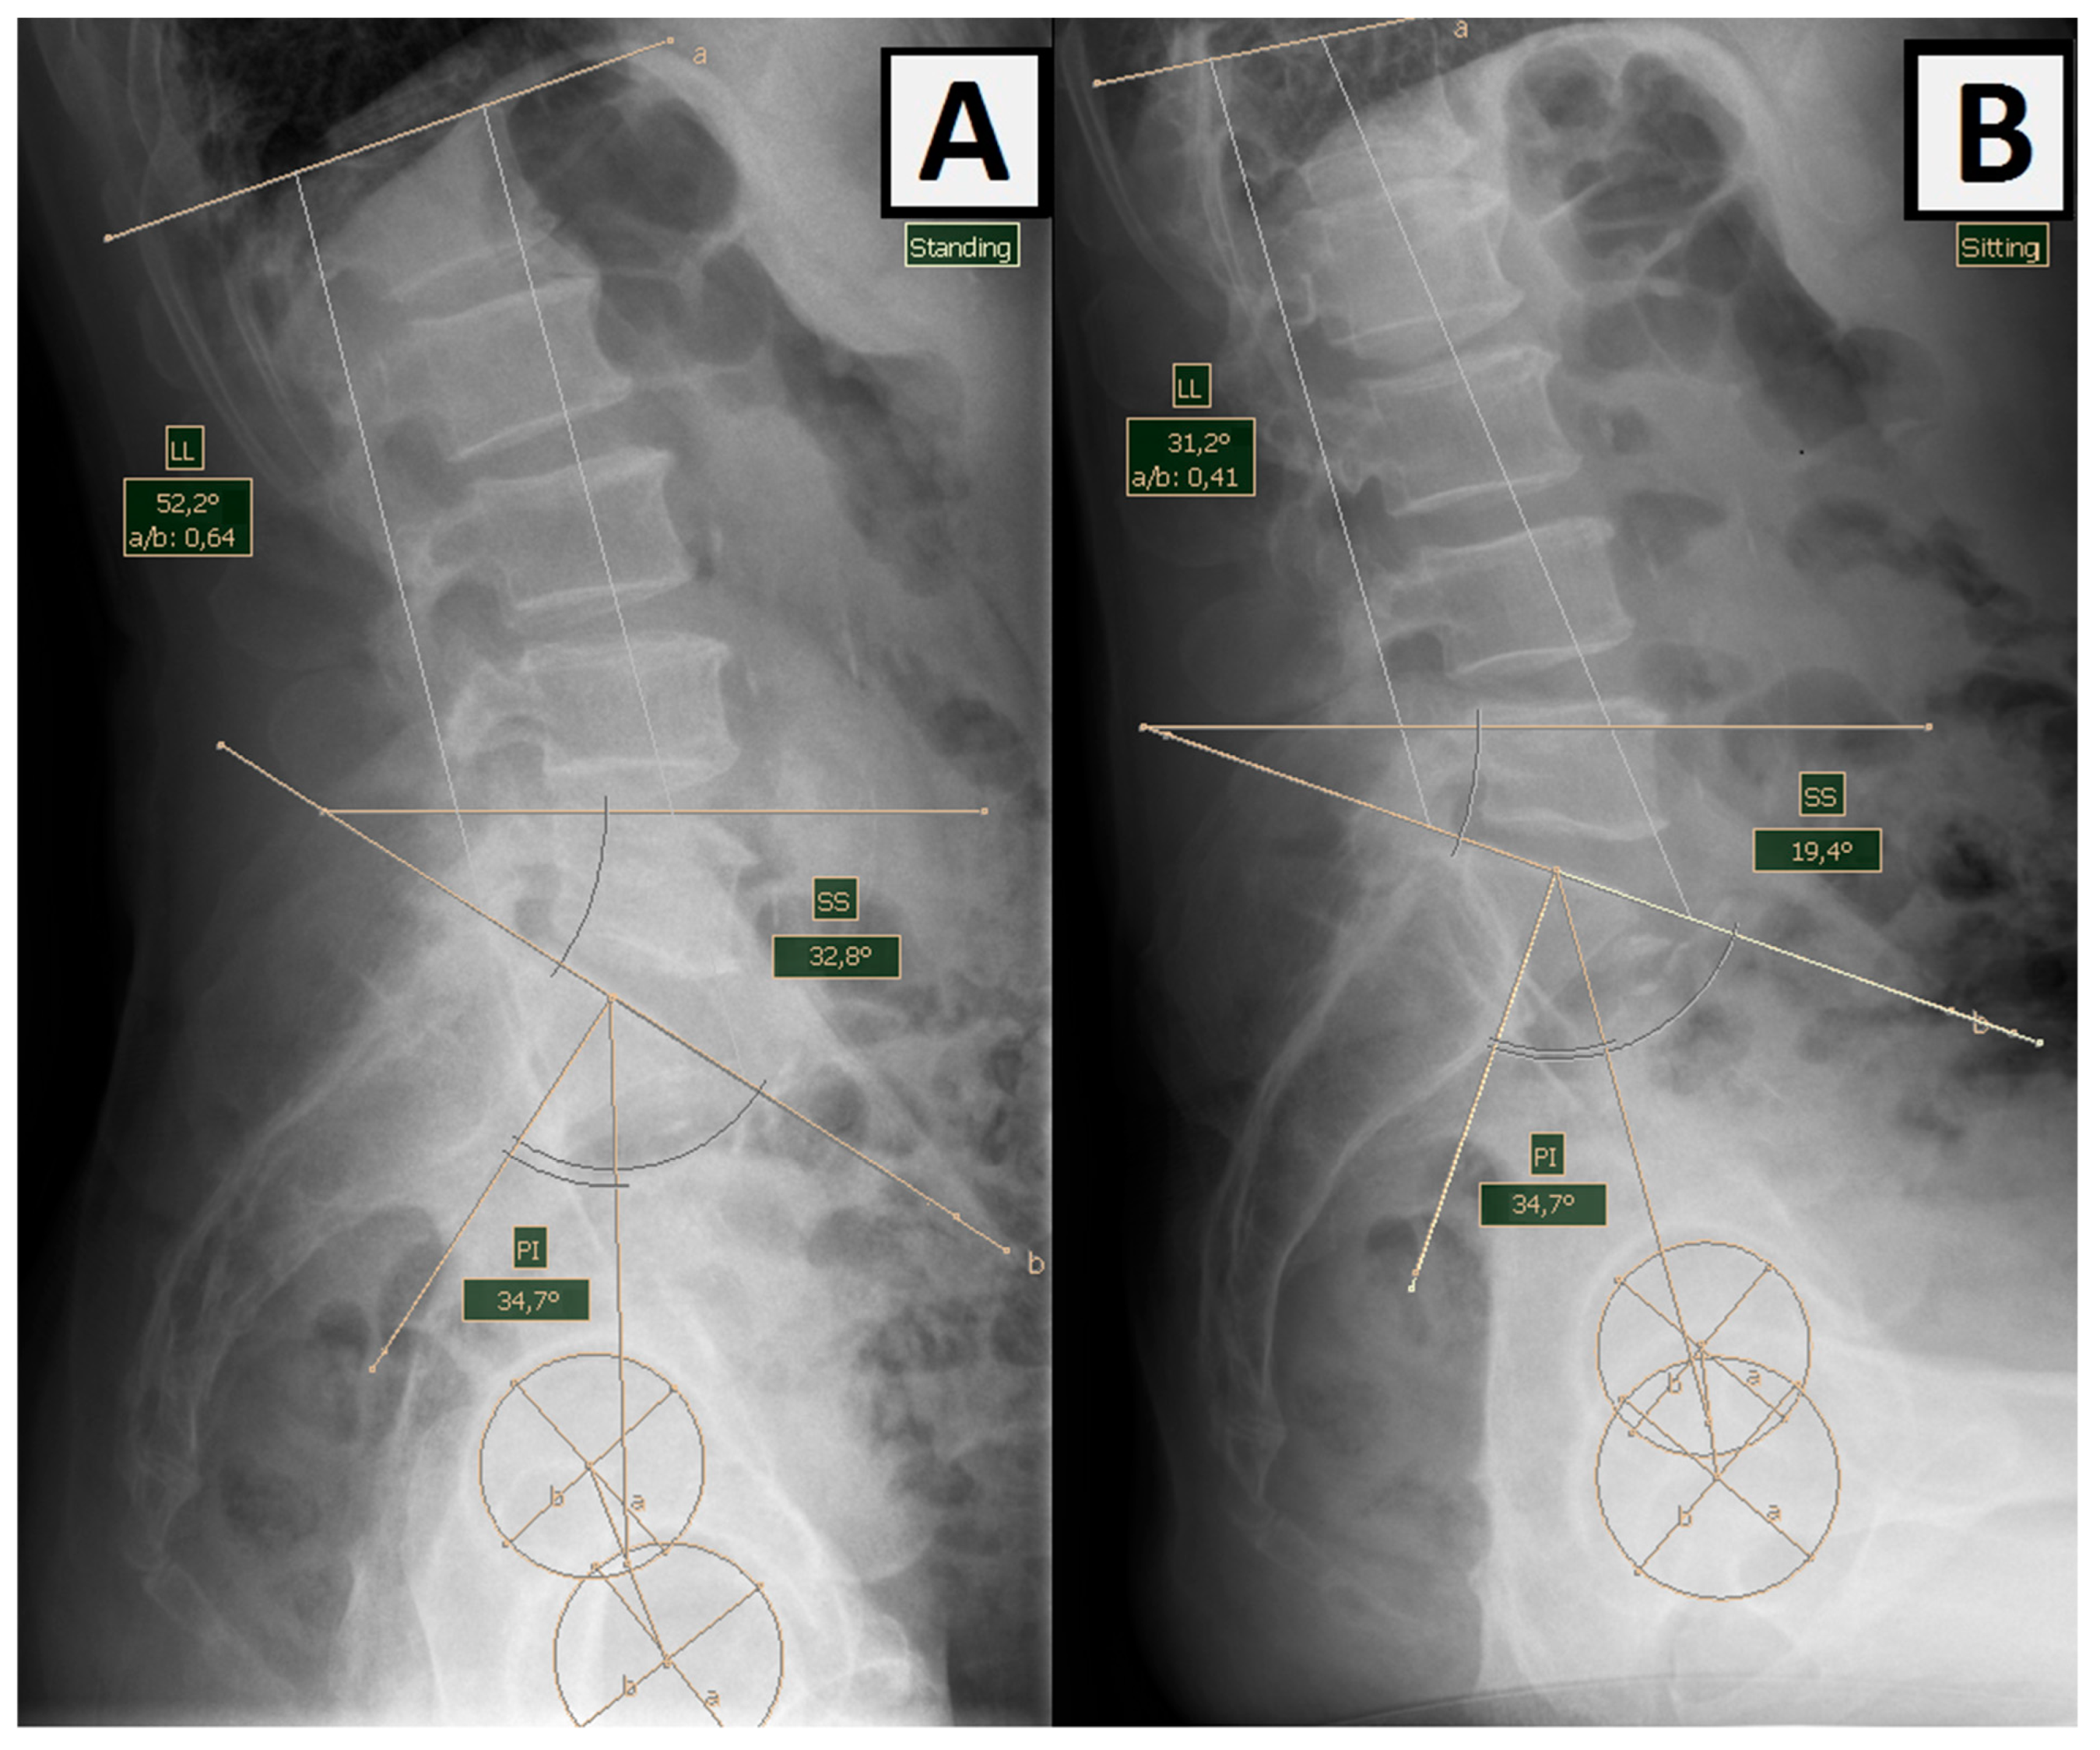

Pelvic incidence (PI)—lumbar lordosis (LL) mismatch (PI-LL)—sagittal lumbar pelvic balance measured in a standing position using PI (the angle between the straight line connecting the center of the femoral heads with the center of the S1 border plate and the line perpendicular to the base of the sacrum) and LL (lumbar lordosis curve angle) (Figure 2) [24]. Pelvic incidence is a morphological parameter that remains constant despite the movement of the spine and pelvis throughout adulthood and does not change as a result of degenerative diseases of the spine. Pelvic incidence-lumbar lordosis mismatch (PI-LL mismatch) is a parameter often used by spine surgeons to define sagittal deformities. For arthroplasty surgeons, it is an important measure to help identify patients with flat deformities of the back resulting from the abolition of lordosis and a posterior tilt of the pelvis in a standing position (Figure 2) [25].

Figure 2. Measurement of lumbar lordosis (LL) and pelvic incidence (PI) angles in (A) standing and (B) sitting positions. The ∆LL of this patient is 21°, while the PI remains unchanged 34,7°. PI-LL measured in an upright position is −17.5°.